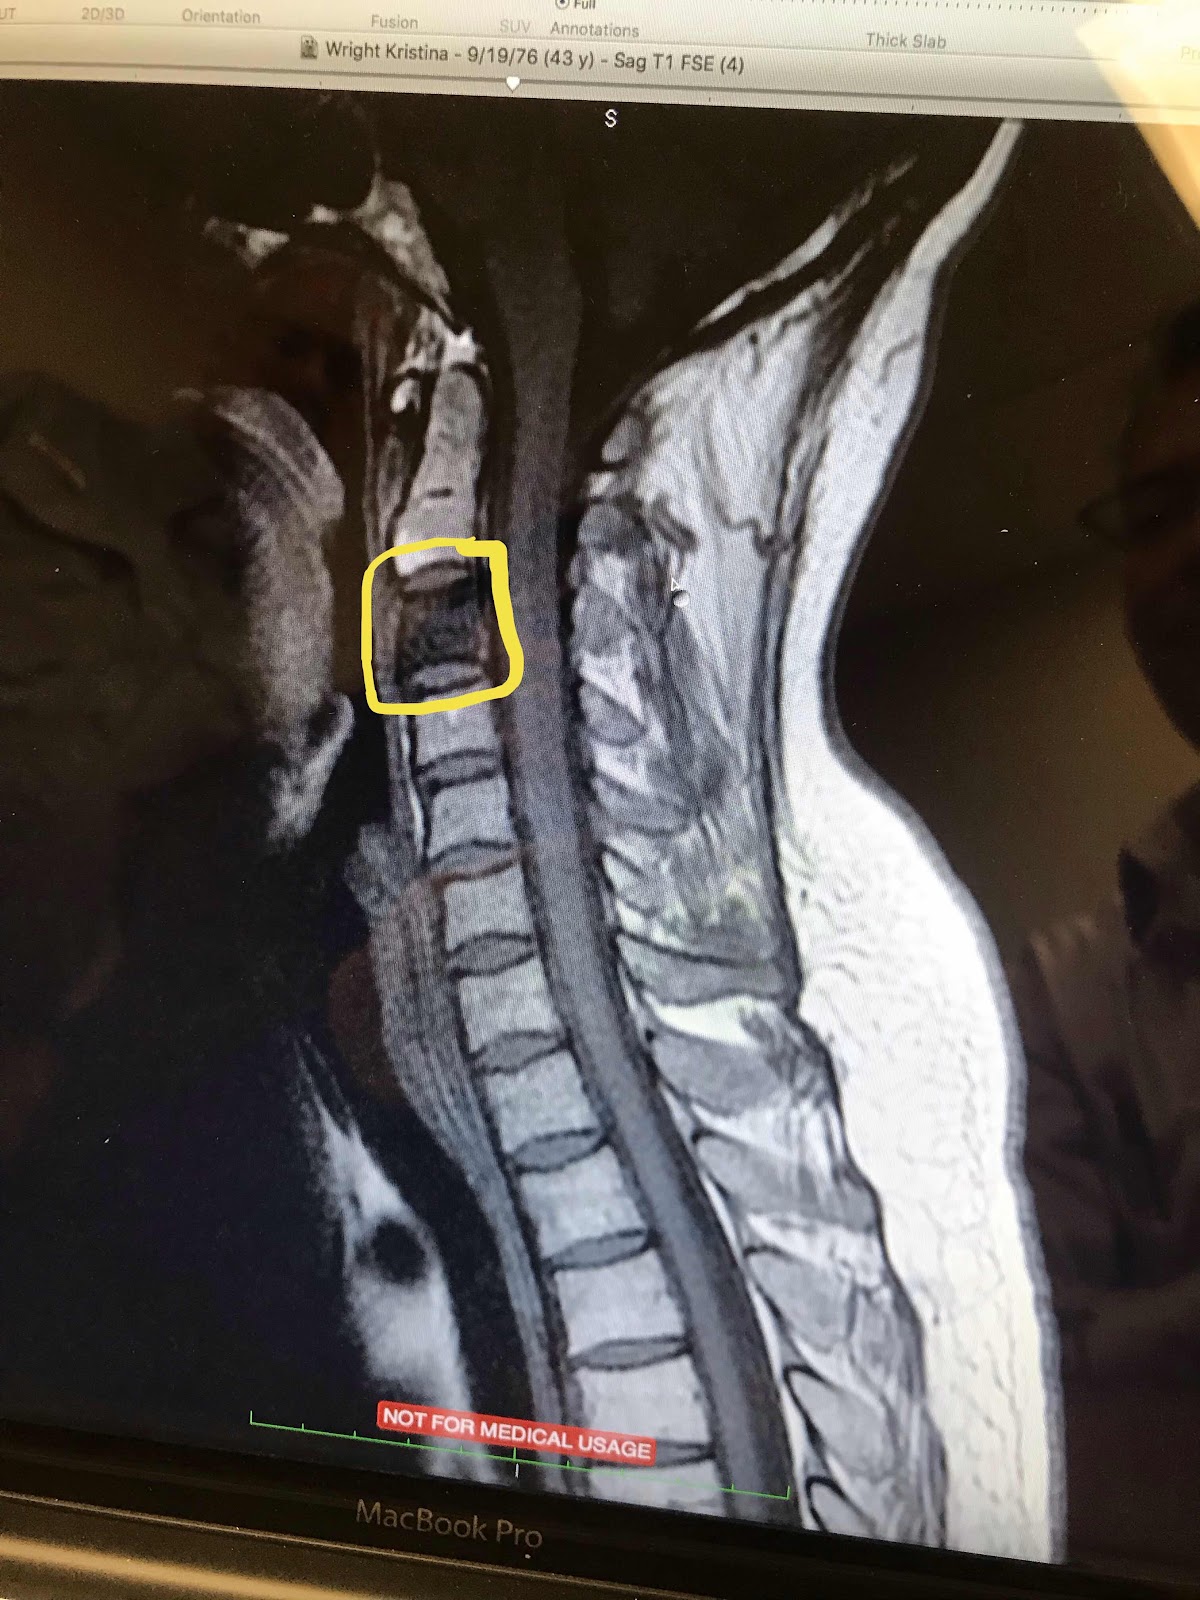

New Cancer in neck found. Had an insane asylum creepy-type experience having a giant wet, hot mold formed around my head, neck and shoulders and bolted to a table to keep me still. I radiated it. Thought I was in the clear. 8 days later, last two days of Alyssa’s Pageant trip to CA I got a terrible raw throat, infection, extreme fatigue, muscle weakness, vomiting. Got meds. Wrong meds. Got fluids. No help. Finally right meds and steroids. Recovered.

New cancer found in right side of my brain. Today we left the house at 8:15 am and got home at 6:15 pm. Used that same molded mask bolted to the table. I radiated it. Got immunotherapy infusion. Started with energy and ended physically exhausted, even on steroids. Told I will lose my hair in the size of a quarter, possibly forever. They don’t know as everyone’s different. Told I’ll have swelling and headaches. Told I could have a brain misfiring causing me to have seizures.